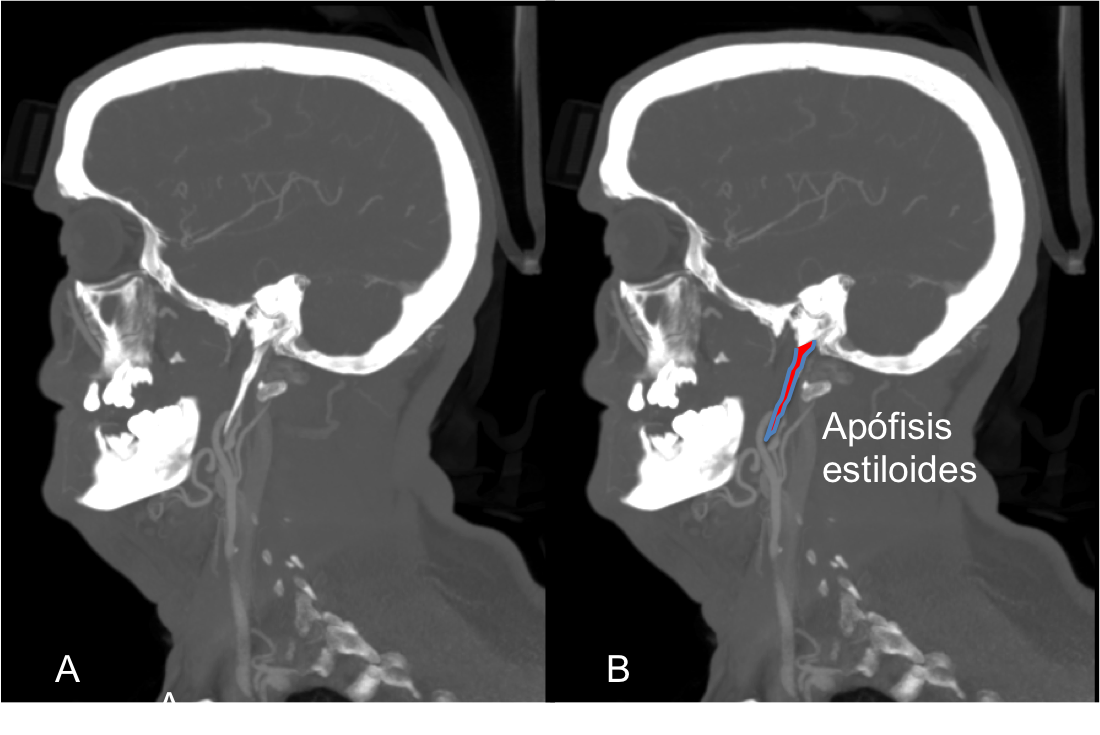

En la Figura 2. se puede observar la apófisis estiloides elongada en relación con el inicio de la disección de la arteria carótida interna izquierda.